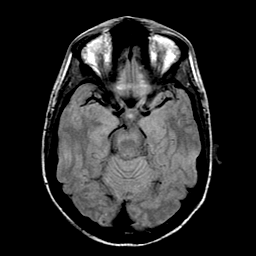

Sarcoma, MR Study #1 mr-pd -- Slice #8

[Home][Help][Clinical] Slice 8